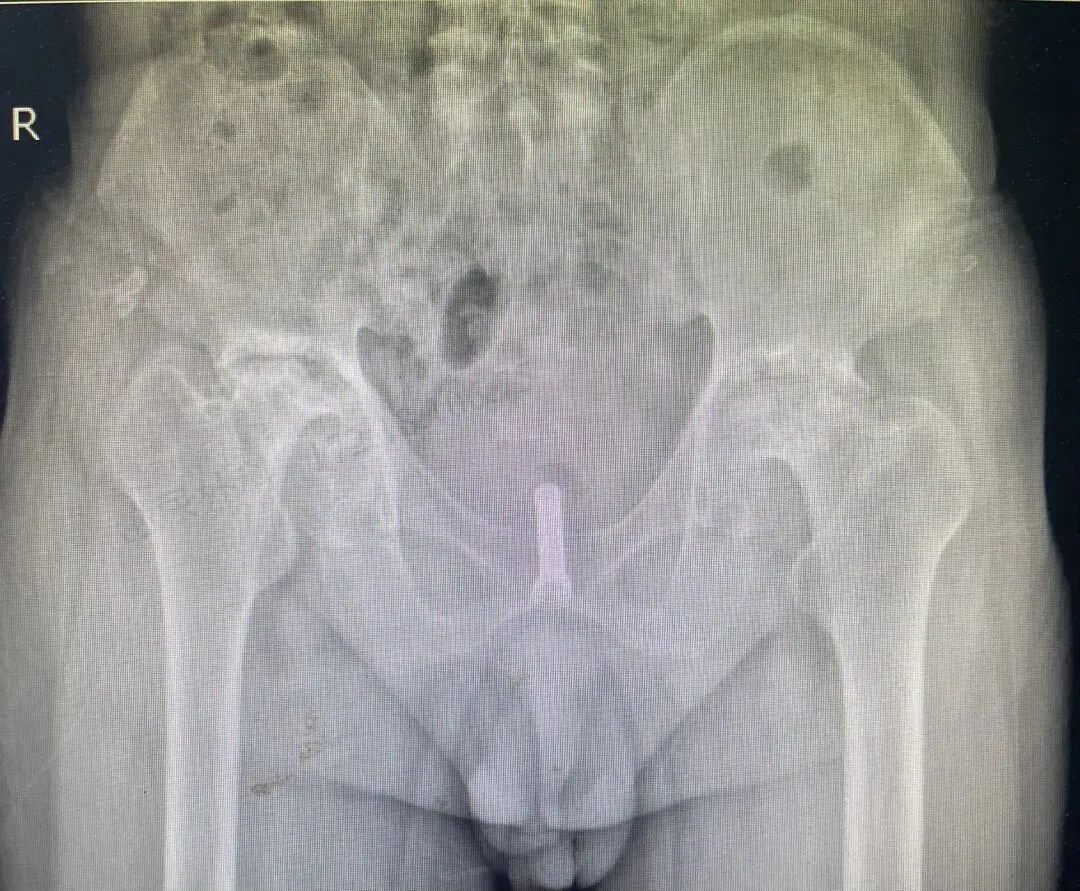

65岁的李先生(化名)长期受前列腺增生困扰,合并膀胱结石病史,曾接受过膀胱切开取石术,但术后仍无法正常排尿,出现尿潴留,不得不长期依赖导尿管生活。更棘手的是,患者还患有双侧股骨头坏死,无法配合常规前列腺手术所需的截石体位,导致传统手术治疗路径受阻。

术前检查发现患者存在严重尿路感染,医疗团队首先进行了抗感染治疗。待感染控制后,手术团队利用膀胱软镜,成功将前列腺支架精准置入患者前列腺尿道并妥善固定。整个手术过程顺利,无需特殊体位,完美规避了患者股骨头坏死带来的手术障碍。